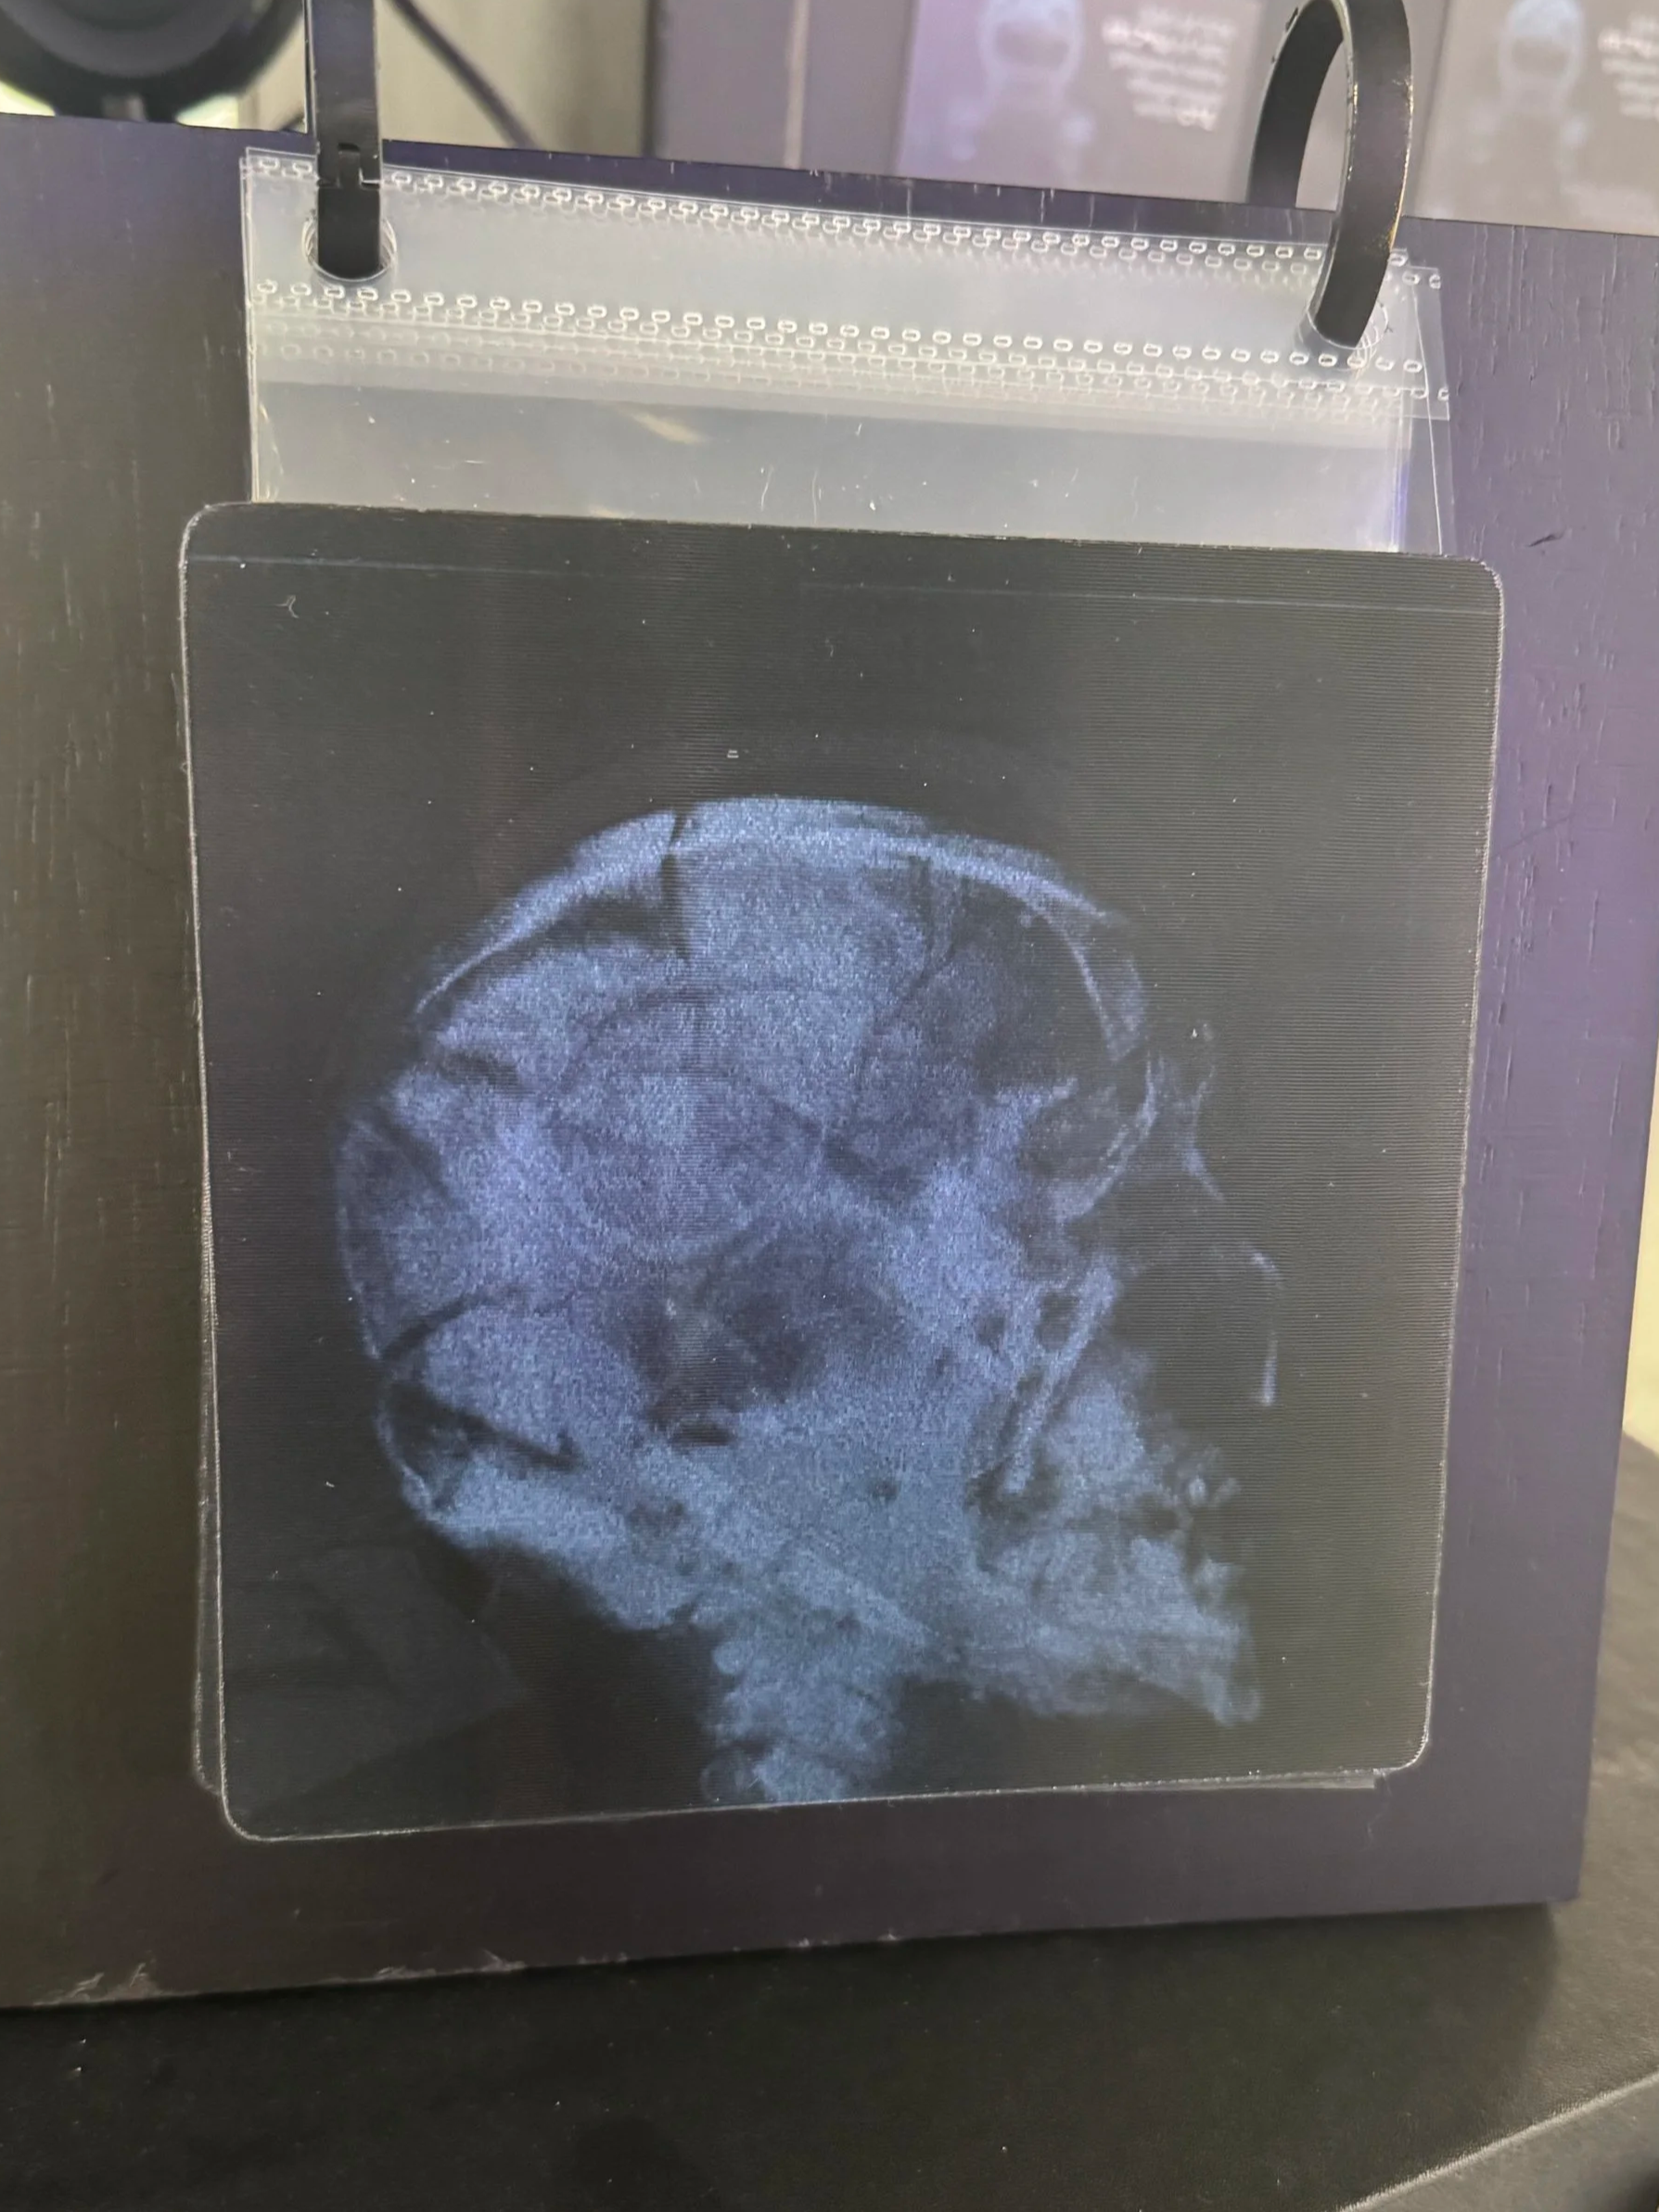

Lenticular Print Series

A series of lenticular prints presents dual-image comparisons that shift as the viewer moves.

Content Includes:

• Healthy brain vs. advanced CTE degeneration

• Suicide rates with CTE vs. without

• Perception vs. long-term reality